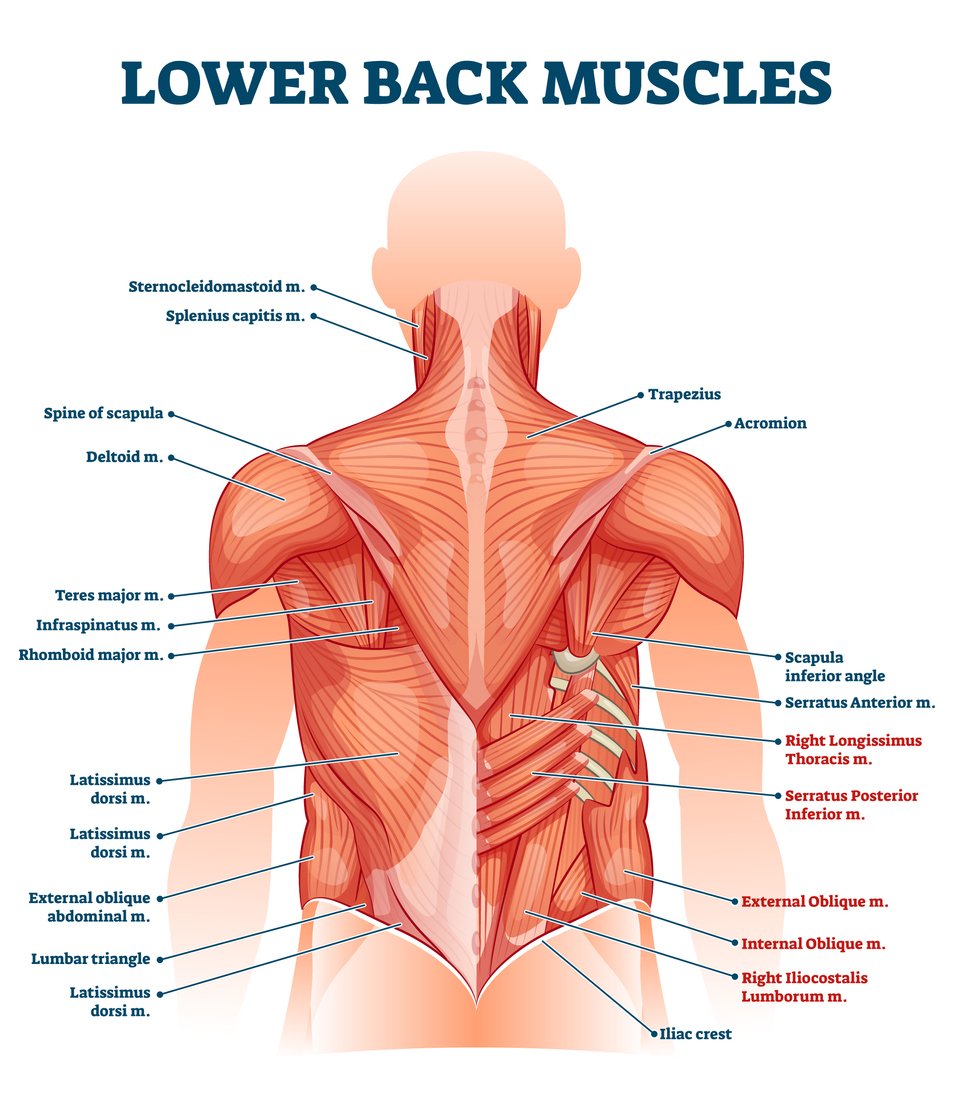

Fitness: My Muscles | Body muscles names, Total body workout, Muscle names

Fitness: My Muscles | Center for Young Women’s Health

Lower back muscles labeled educational anatomical scheme vector …

Lower Back Muscle Anatomy and Low Back Pain

Anatomy Of Female Human Body From The Back – Male Muscle Model – As …